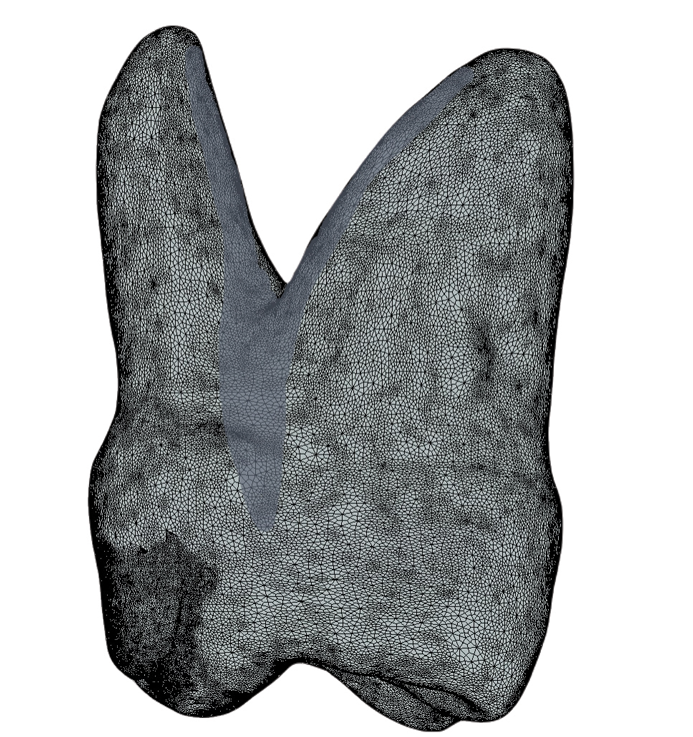

The canine fossa, a distinct anatomical feature, is the concavity on the mesial crown and root surface of the maxillary first premolar (Figure 1). This concavity extends from the crown into the root trunk, distinguishing it from the convex mesial crown surface of the second premolar. Larger and deeper than the incisive fossa, the canine fossa is separated by the vertical ridge of the canine eminence, which corresponds to the canine tooth socket.

(1.) A 3D image of the mesial aspect of a maxillary first premolar showing the canine fossa concavity extending from below the contact point onto the root surface.

Figure 1

(7.) A 3D image of the mesial aspect of a maxillary first molar with the challenging concave region leading to the furcation shaded.

Figure 7